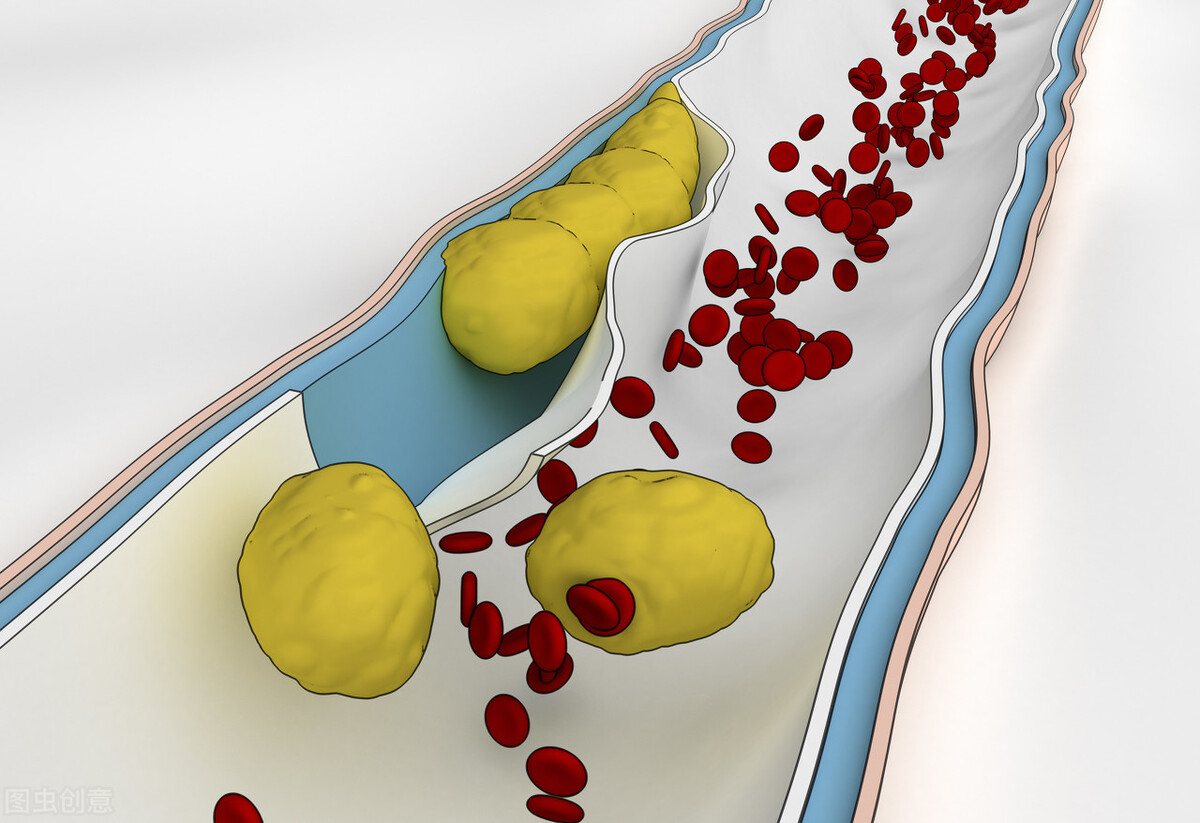

心肌梗死往往是不稳定的斑块破裂后,激活了血管内凝血,导致血栓形成才发生的。

冠心病的发病基础就是体内的脂代谢异常,导致冠脉内膜下脂质沉积,进一步发展为冠脉斑块。与冠心病关系最密切的血脂,就是低密度脂蛋白胆固醇。

斑块在没有完全钙化之前,都是不稳定斑块,有破裂的可能。一旦斑块破裂,就有可能导致血栓形成,进而导致心肌梗塞。因此,冠心病患者还要服用预防血栓形成的药物。